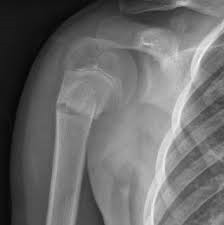

• Знаете ли вы, как лечат переломы проксимального отдела плечевой кости?

Знаете ли вы, как лечат переломы проксимального отдела плечевой кости?

Переломы проксимального отдела плечевой кости являются одними из наиболее частых переломов в травматологической ортопедии, а большинство переломов проксимального отдела плечевой кости у пожилых людей представляют собой низкоэнергетические остеопоротические переломы.